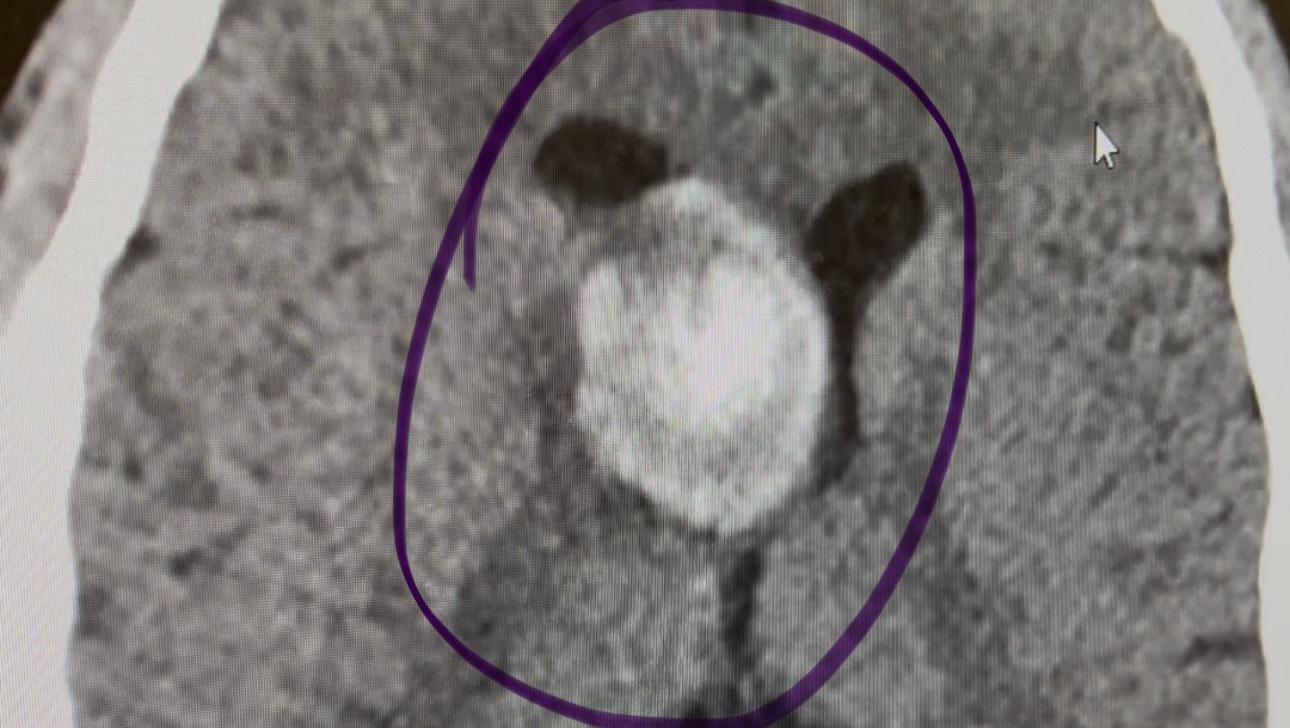

We are reaching out to ask for your support for Eric Chavez, who is currently facing a serious medical challenge. Eric has been diagnosed with a mass and abnormal growth on his brain, requiring surgery and extensive recovery time.